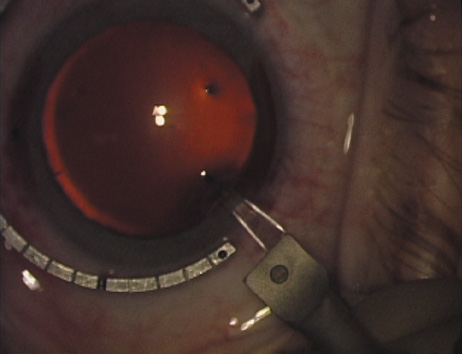

Case 2 is a 79-year-old woman who presented with a very dense left cataract. Her refraction was recorded at −2.25 +2.75 × 125 with a difficult end point. Her manual keratometry and topography measurements were consistent and revealed slightly less than 1.75 D at 120 degrees. Because of the questionable refraction, greater value was placed on the corneal measurements. Based upon the cataract nomogram, the plan was for paired LRIs of 40 degrees to be placed over the steep 120-degree axis (Figs. 1219).

Fig. 14. The incision is completed. (Reprinted from Hardten DR, Lindstrom RL, Davis EA. Phakic Intraocular Lenses: Principles and Practice. Thorofare, NJ: SLACK Incorporated, 2004, with permission.)

Fig. 15. Total arc length equals 40 degrees. (Reprinted from Hardten DR, Lindstrom RL, Davis EA. Phakic Intraocular Lenses: Principles and Practice. Thorofare, NJ: SLACK Incorporated, 2004, with permission.)